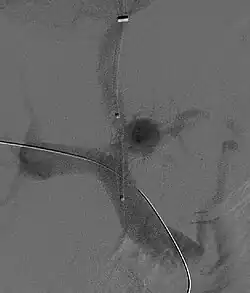

Przezszyjne wewnątrzwątrobowe zespolenie wrotno-układowe (używany jest skrótowiec TIPS lub TIPSS, od ang. transjugular intrahepatic portosystemic shunt) – połączenie między gałęzią żyły wrotnej a jedną z gałęzi żył wątrobowych, za pomocą stentu. Jego założenie odbywa się z dostępu przez żyłę szyjną wewnętrzną, przy zastosowaniu technik angiograficznych.

Zabiegu dokonuje się z dojścia przez żyłę szyjną wewnętrzną. Po zacewnikowaniu żyły wątrobowej wprowadza się długą, zakrzywioną igłę lub system współosiowy i pod kontrolą ultrasonograficzną dokonuje przekłucia do gałęzi wewnątrzwątrobowej żyły wrotnej. Kanał przekłucia poszerza się do średnicy 8–10 mm i stentuje na całej długości. W razie konieczności dostęp można wykorzystać do doraźnej embolizacji żylaków przełyku. Następnie mierzy się gradient między układem wrotnym a systemowym; nie powinien on przekraczać 12 mm Hg.